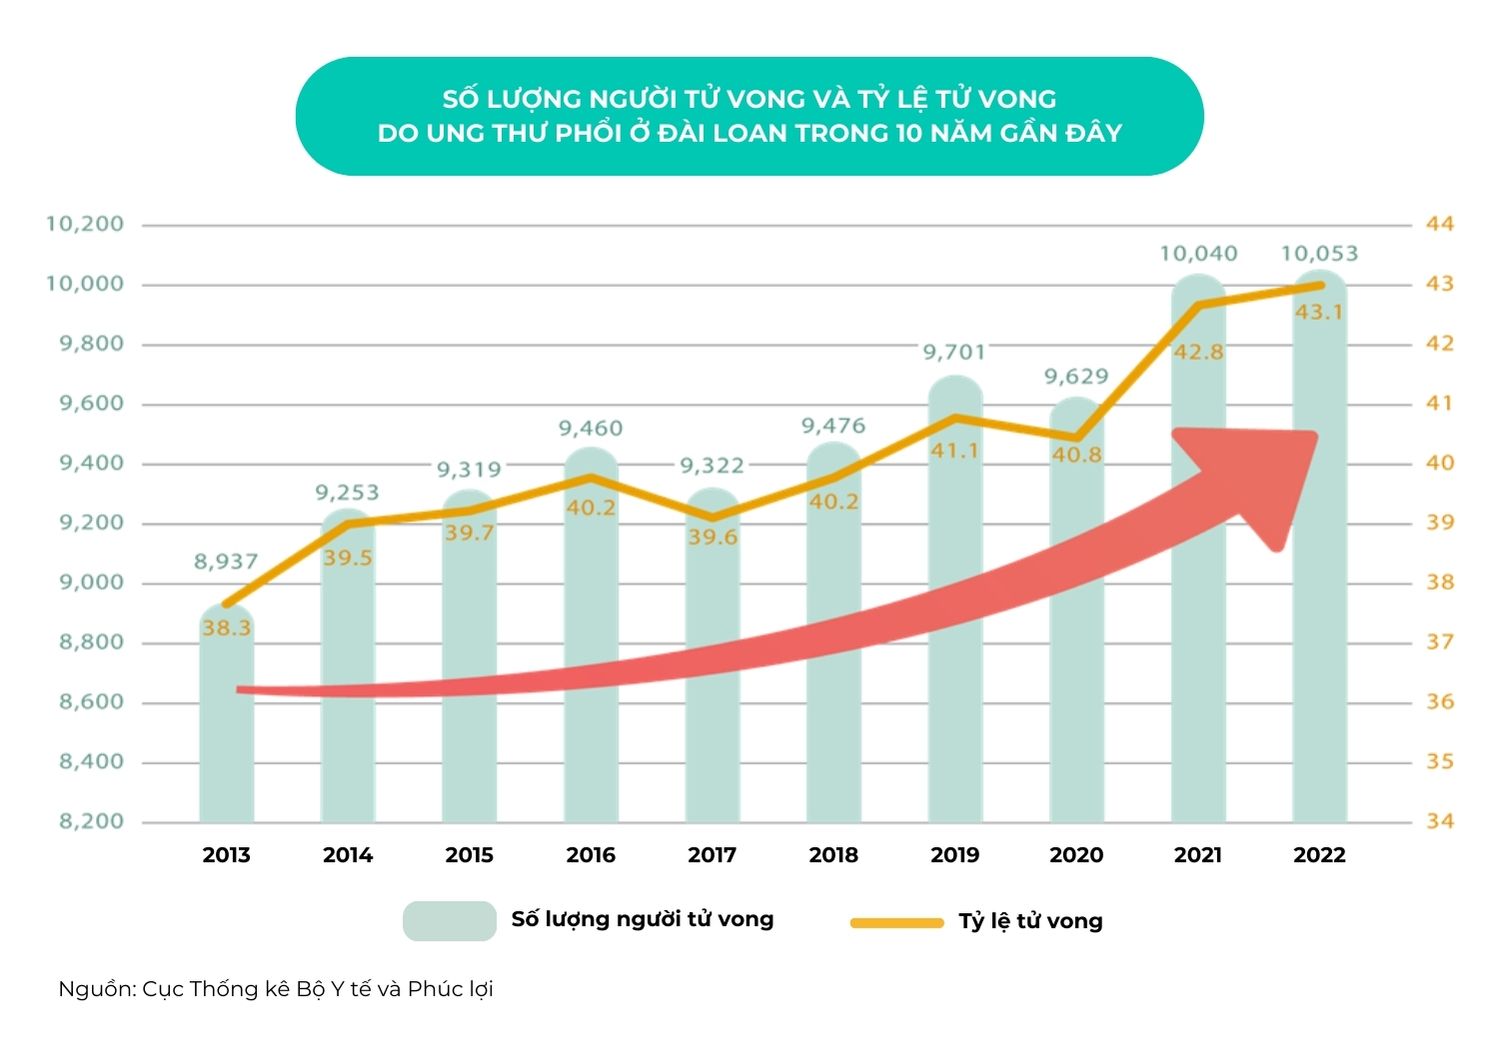

Ung thư phổi - Cảnh báo khẩn cấp cho Đài Loan

- Ung thư phổi: không chỉ là căn bệnh ung thư gây tử vong nhiều nhất trên toàn cầu, mà còn là nguyên nhân dẫn đầu về tử vong do ung thư ở Đài Loan trong suốt 18 năm liên tiếp. Điều đáng chú ý hơn là, đây không đơn thuần chỉ là con số “vô tri” mà đó còn là những câu chuyện đau lòng của không ít gia đình trong suốt nhiều năm.

- Trong 5 năm qua: số người tìm đến điều trị y tế cho bệnh ung thư phổi đã tăng từ 61.000 người vào năm 2017 lên 87.000 người vào năm 2022. Những con số đáng kinh ngạc này nhắc nhở chúng ta về sự quan trọng của phòng ngừa và phát hiện sớm.